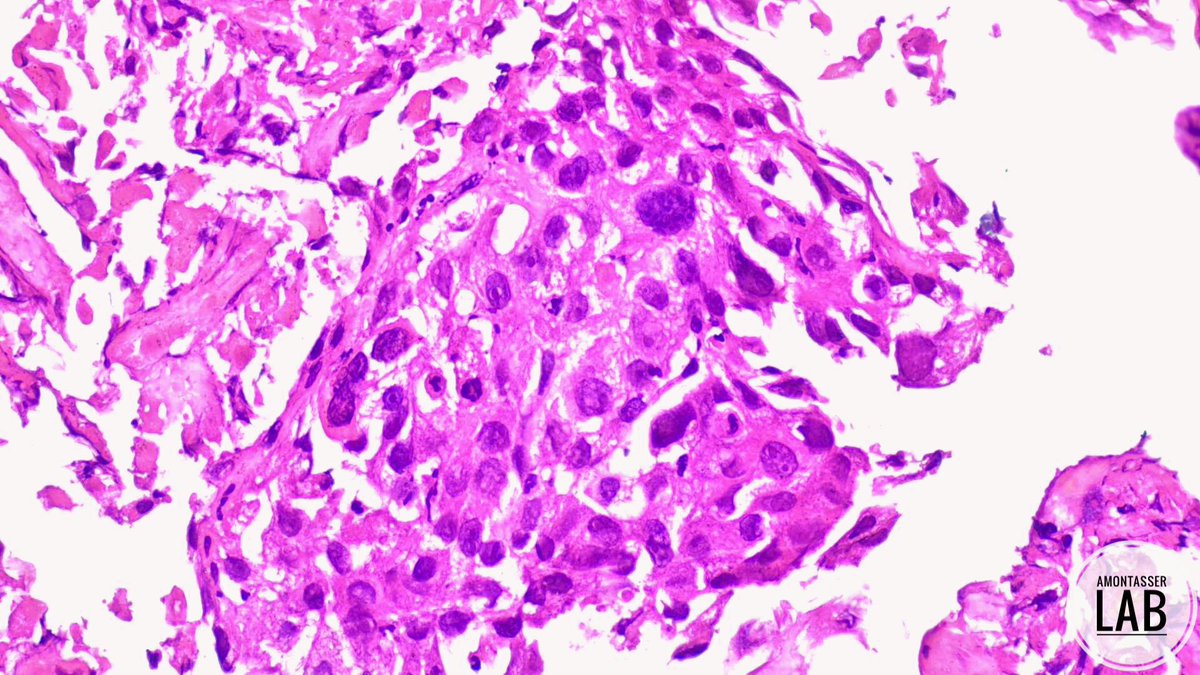

M 40+ Gallbladder fossa mass infiltrating liver 🫤 Cellblock of EUS-FNB🔬 How would you report this 🧐 #Cytology #Pathology #GIpath #PathTwitter #PathX